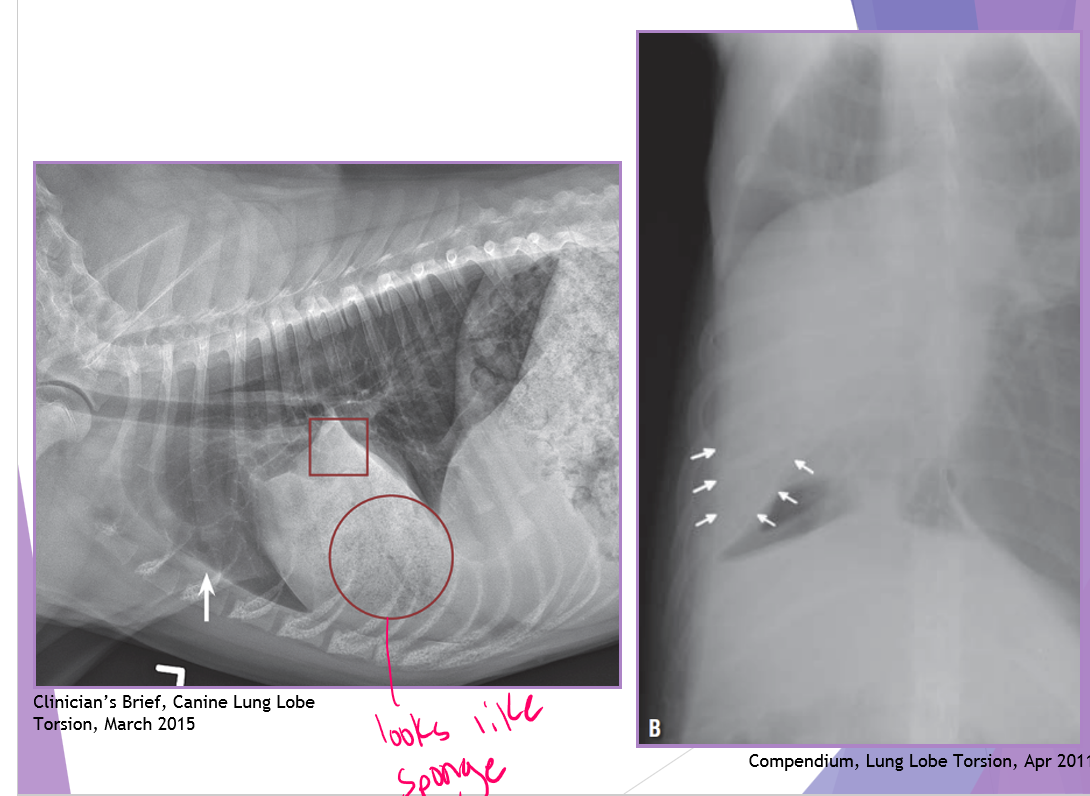

complete lobectomy - Torsion

signalment - deep, narrow chest

right cranial and middle are most common

venous and bronchus obstruction arterial flow remains

lobe becomes congested and consolidated

surgery

complete lobectomy WITHOUT untwisting the lobe